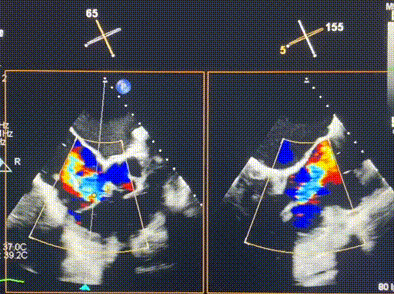

術(shù)前超聲提示重度三尖瓣反流

接受本次LuX-Valve Plus治療的是一位三尖瓣重度反流的高齡女性,患者早前曾由于二尖瓣疾病行經(jīng)導(dǎo)管二尖瓣置換術(shù),植入Tendyne瓣膜一枚,且有ICD植入史。術(shù)前CT分析結(jié)果顯示,瓣環(huán)大小為47.6mm,血管無(wú)明顯迂曲和鈣化。由于患者三尖瓣解剖結(jié)構(gòu)復(fù)雜,二尖瓣位人工瓣膜造成的超聲偽影和ICD導(dǎo)線的干擾使得歐洲沒有其他合適的商業(yè)化和臨床試驗(yàn)的產(chǎn)品可以對(duì)其進(jìn)行治療。經(jīng)過(guò)Rodrigo Estévez-Loureiro教授團(tuán)隊(duì)的詳盡術(shù)前評(píng)估,認(rèn)為L(zhǎng)uX-Valve Plus經(jīng)導(dǎo)管三尖瓣置換系統(tǒng)可以對(duì)該患者進(jìn)行有效的治療。因此,Rodrigo Estévez-Loureiro教授團(tuán)隊(duì)最終決定使用這一中國(guó)創(chuàng)新器械為患者進(jìn)行手術(shù)。法國(guó)波爾多里爾大學(xué)附屬醫(yī)院的Thomas Modine教授與加拿大圣保羅醫(yī)院的Anson Cheung教授全程線下指導(dǎo)本次手術(shù)。